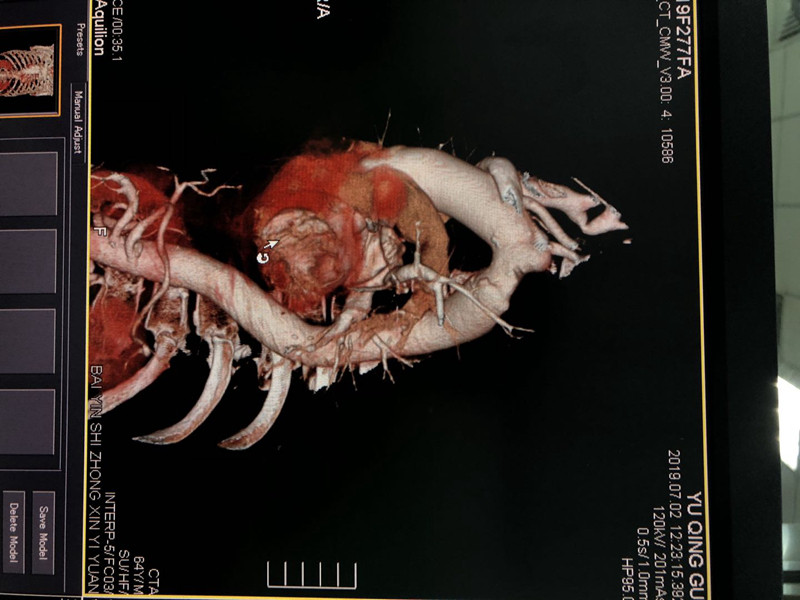

近日,我院介入医学科收治一名中年男性患者,主因“右侧肢体偏瘫”入院,急查发现患者脑出血,并发主动脉壁内血肿形成,给予锥颅脑内血肿引流后成功行主动脉腔内隔绝术,术后患者病情已趋于平稳,恢复良好。

该手术是我院、也是本地区首例主动脉壁内血肿腔内隔绝术,标志着我院的医疗技术水平上了一个新台阶,为我院以后开展急性动脉夹层手术提供技术储备,造福我区乃至整个白银市的患者。